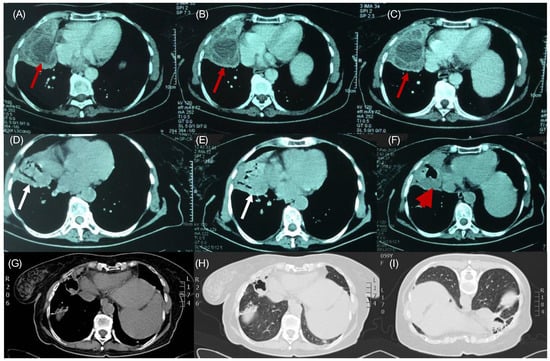

Recurrent Echinococcosis Exhibiting Hydatoptysis: A Rare Case with Imaging Insights

2. Case Presentation